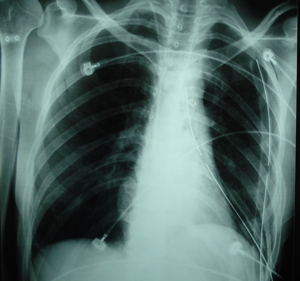

Οπισθιοπροσθία ακτινογραφία θώρακος. Διακρίνεται διεύρυνση του μεσοθωρακίου που οφείλεται στην ύπαρξη όγκου στο μεσοθωράκιο.

Μετεγχειρητική οπισθιο-πρόσθια ακτινογραφία θώρακος μετά από μέση στερνοτομή και αφαίρεση του όγκου. Η ιστολογική εξέταση έδειξε ότι πρόκειται για σπάνιο όγκο, προερχόμενο από έκτοπο θυρεοειδικό ιστό.